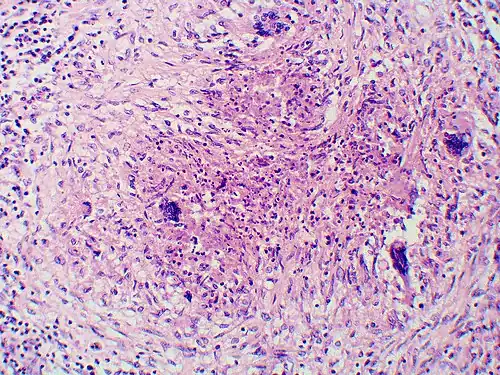

Once suspected, the diagnosis of blastomycosis can usually be confirmed by demonstration of the characteristic broad-based budding organisms in sputum or tissues by KOH prep, cytology, or histology.[27] Tissue biopsy of the skin or other organs may be required to diagnose extra-pulmonary disease. Blastomycosis is histologically associated with granulomatous nodules.

-

Granuloma with early suppuration. The fungal organisms are difficult to recognize at this low magnification. -